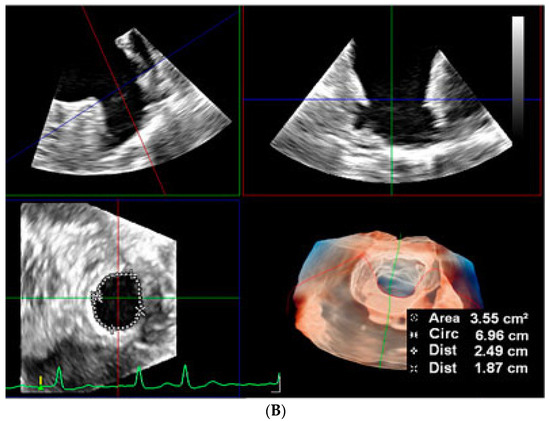

2.2.2. LAA Measurements (Anatomy and Morphology)

2.2.3. Intra-Procedural TOE